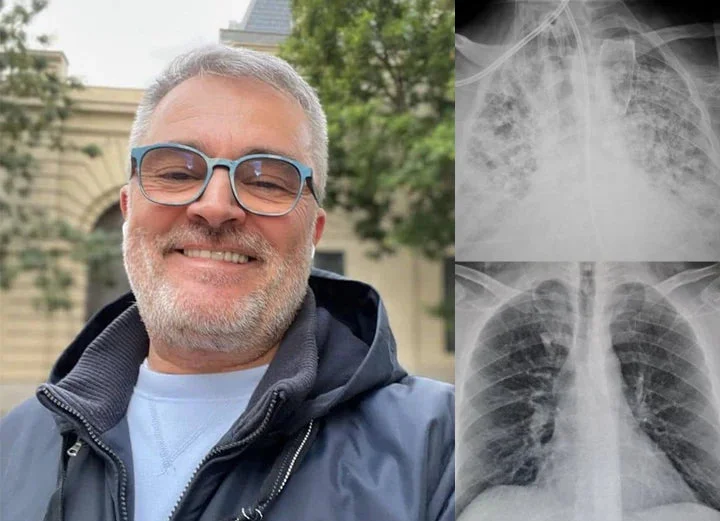

“l’ve spent most of my career on construction sites, constantly exposed to dust and airborne pollutants. Over time, it caught up with me-l developed COPD. At first, it was just mild shortness of breath, but the symptoms slowly worsened.l found myself coughing regularly, wheezing, and relying on an inhaler just to get through the day. Even climbing stairs became a challenge. My doctor warned me that if l didn’t take action, my condition could severely impact my quality of life.”

“By the fourth week, the tightness in my chest had lessened dramatically.l had more energy, and my doctor was surprised to see such a reduction in lung inflammation. Even my family noticedl wasn’t using my inhaler as much and seemed more active and upbeat.”

Now, seven weeks in, l can say with confidence that Mullein Aroma Diffuser has changed my life. My lungs feel stronger. The coughing,wheezing, and constant fatigue are gone.l can walk. play with my kids, and enjoy the outdoors again-without struggling to catch my breath. This product gave me back the ability to live fully.l recommend it to anyone battling COPD or breathing difficulties.lt brought me not just relief_but real hope.“

Max Winters- California